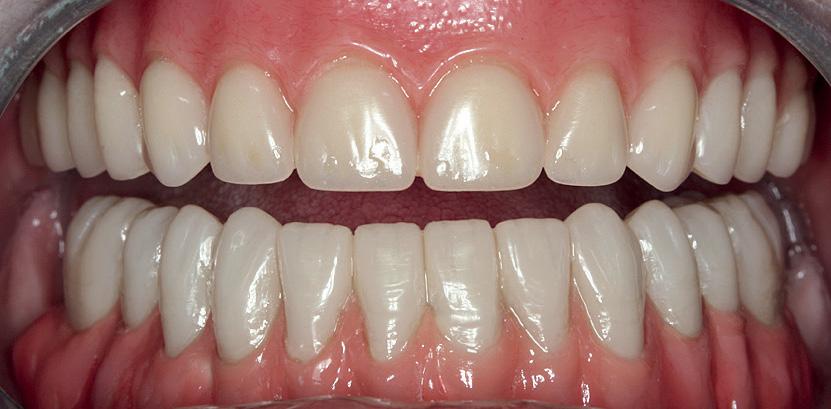

To achieve good primary closure, it was decided to modify the procedure and trim the roots up to the furcation to ensure a sound collar of alveolar bone and advance the buccal flap. This modification helped significantly during primary closure of the socket. LL8 tooth was removed completely as the roots became loose as well as UR8 and LU8. The post-operative phase was uneventful, and she recovered well (Fig 4).